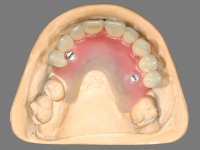

Paciente do sexo feminino, com 52 anos, não fumadora e portadora de uma prótese parcial removível acrílica superior e inferior. No maxilar superior estavam presentes os dentes 1.6/1.5/1.3 e 2.7. O canino apresentava-se com extração indicada. No maxilar inferior estavam presentes os caninos e os incisivos. As próteses removíveis utilizadas não estavam em boas condições. A paciente apresentava uma falta de apoio significativa do lábio superior mas as zonas edentulas do maxilar superior eram compatíveis com a colocação de implantes.

Inicialmente foram confecionadas duas novas próteses removíveis. O dente 1.3 foi extraído quando da colocação das próteses. Feito o estudo imagiológico necessário, foram colocados 4 implantes no maxilar superior. Após 3 meses de osteointegração foi feita a impressão para a confeção de ceras de articulação montadas em placa base aparafusadas aos implantes. Estas ceras foram utilizadas na recolha das relações inter-maxilares e na tentativa de proporcionar apoio ao lábio superior. Foi feita a prova de dentes com estes montados em placas base aparafusadas permitindo uma avaliação estética dinâmica muito interessante. Sendo validada esteticamente pela paciente, esta prova deu origem a uma muralha de silicone que orientou laboratorialmente a confeção da infraestrutura metálica. A infraestrutura metálica com os dentes montados em cera foi provada em boca, permitindo simultaneamente verificar a sua adaptação bem como a estética final. O trabalho final foi colocado em boca sendo acompanhado de instruções rigorosas de técnicas de higiene oral bem como da informação da necessidade de consultas de controlo periódicas.